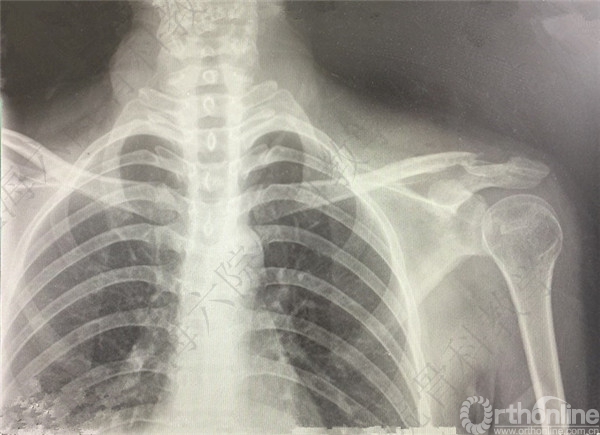

患者跌倒至左锁骨远端骨折。

CT示:左锁骨远端骨折,远端骨块向前下方移位。

患者择期行左锁骨远端骨折切开复位内固定术。